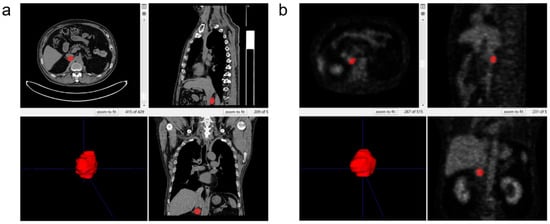

2.5. Three-Dimensional Segmentation